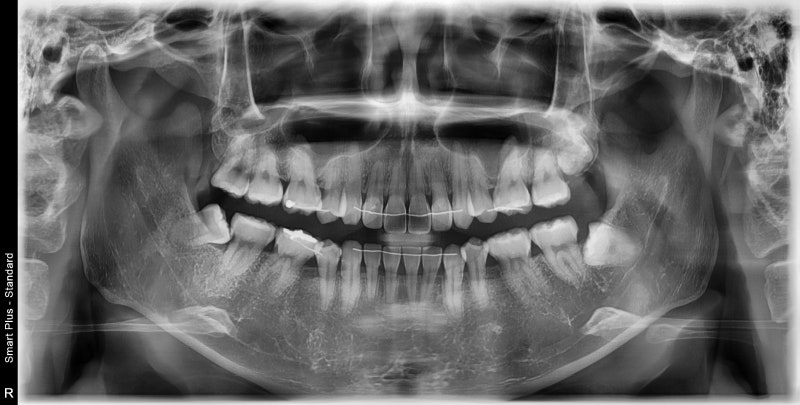

사랑니 발치를 위해 내원한 환자분의 사연입니다. 간단한 구강검진에도 메스꺼움 때문에 입을 보는 것조차 힘들었습니다. 이전에는 스케일링이 어렵다고 하셨는데 사랑니가 심하게 나와서 제거해야 했습니다. 이런 일이 있다는 건 알지만 수면 마취를 하지 않으면 메스꺼움이 꽤 심하기 때문에 걱정할 것이 많다고 생각합니다. 메스꺼움의 원인은 다양하기 때문에 단순히 수면마취로 해결되지 않는 심한 메스꺼움인 경우도 있지만, 이전 치과 치료의 트라우마나 나쁜 기억으로 인한 반사적 거부반응으로 메스꺼움이 나타나는 분들은 수면마취로 메스꺼움을 줄일 수 있습니다. 이 환자의 경우 양치질을 하거나 식사를 할 때 토하지 않는 사람이었고, 진정마취로 정서적 안정을 취했다면 진정이 일어나지 않았을 것으로 판단했다. 발치 전 CT 영상 분석입니다 안전한 발치를 위해서는 진정 및 마취 전 충분한 분석이 필요합니다 수면마취 시간을 최소화하고 안전하게 발치하는 방법을 확인하세요 이것은 환자의 엑스레이입니다. 누워있는 사랑니 2개와 위의 과잉치까지 볼 수 있습니다. 이 환자분도 오른쪽 위 사랑니 옆에 여분의 치아가 있었습니다. 사진에 미니 조개가 보이시나요? ^^) 사랑니 옆 오버레이 입니다. 소요 시간은 마취 준비 및 기상 1시간 + 발치 1시간입니다. 아니나 다를까 1차 구술 시험은 내가 할 때보다 덜 구역질이 나고 환자와 의사팀이 많이 고생했지만 후송은 순조롭게 진행됐다. 진정 후 사랑니 발치 사진입니다. 위, 아래, 좌우 사랑니 흔적이 있는데 발치 후 엑스레이 사진으로 뼈를 최소한으로 제거하고 치아를 발치하였기 때문에 치아의 흔적만 보입니다. 마취가 풀린 후에는 치료 전과 후의 기억이 없기 때문에 환자도 치료가 끝난 것처럼 일어나기를 좋아합니다. https://blog.naver.com/dentist_ahn/222762850355 연세백스치과병원 수면치료 후기 모음 연세배스치과병원 안양치과병원 수면치료 모음 blog.naver.com 사랑니 발치 외에도 근관 치료, 치과 임플란트 등과 같은 다른 치과 치료도 진정 및 마취하에 수행할 수 있습니다. 수면마취?저희치과에 많은 분들이 후기를 남겨주시고 남겨주신 댓글들을 정성스럽게 모아놓은 글이 있으니 수면치과치료가 궁금하시다면 꼭 보시길 추천드립니다. 안양 수면마취치과 연세베세치과 입니다. 수면마취에 대해 궁금하신 사항이 있으시면 아래 네이버플레이스 링크를 클릭해주세요. 설명하겠습니다. ^^ 경기도 안양시 동안구 평촌대로 223번길 52 원천빌딩 4층 연세베스트치과의원